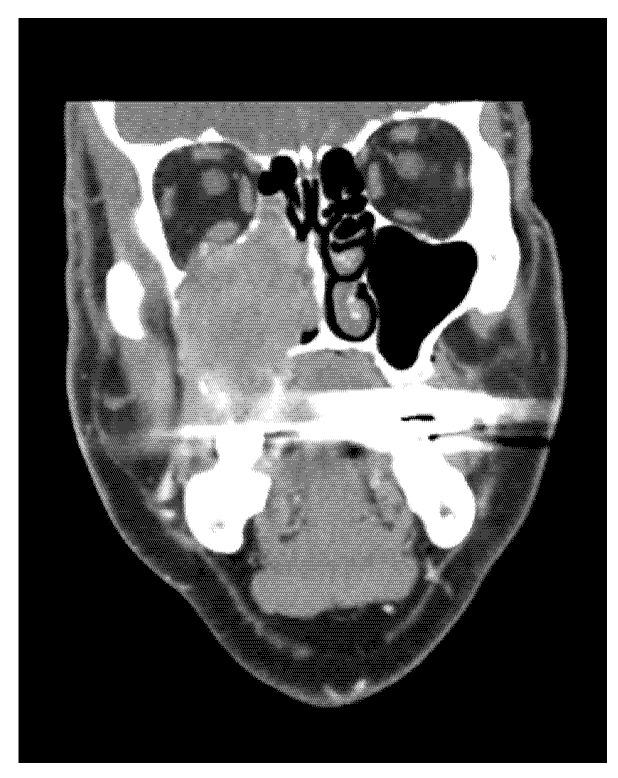

Sarcomas in the head and neck area are rare diseases with an incidence of under 1% of all head and neck malignant tumours. Osteosarcomas or osteogenic sarcomas consist of neoplastic cells that produce osteoid bone or immature bone. Sarcomas develop more in the mandible than the maxilla. The exact diagnosis of different types of sarcomas is based on the immunohistochemical investigation. These rare tumours are of mesenchymal origin; osteosarcomas and chondrosarcomas are the most common types-Ewing's sarcomas. The use of proton beam radiotherapy in the treatment of osteosarcoma of the maxilla is rarely reported in the literature. We present a case of successfully treated (surgery and proton beam radiotherapy) poorly differentiated highly aggressive osteosarcoma in the ethmoids and maxillary sinus and morbidity after the treatment. We were presented with a case of a 65-year-old man with anaesthesia and palsy of the right face. The stomatology department performed the extraction of a tooth. One month later, the wound was still open. The histology showed an osteogenic sarcoma in the area of the wound. The oncologist and maxillofacial surgeons in a catchment hospital recommended a nonsurgical approach. Hence, we performed a radical maxillectomy and ethmoidectomy, after which we continued with proton bean radiotherapy. The patient is now five years after therapy without signs of sarcoma; however, he has blindness in the right eye and reduced vision in the left eye, as well as gliosis of the brain, vertigo, tinnitus, trismus, and ancylostomiases. Head and neck osteosarcomas treatment is considered a complex multidisciplinary task. It is currently argued that there is no clear therapeutic protocol for successful treatment. Innovations in treatment modalities such as proton beam radiotherapy appear to have potential, although their effects on long-term morbidity and survival outcomes are still undetermined. We present a rare case report of an osteosarcoma of the maxilla involving an innovative, successful treatment procedure combining surgical excision followed by proton beam radiotherapy. This treatment approach may enable maximum tumour control. This protocol has not been adequately described in the world literature for this diagnosis.

头颈部肉瘤是一种罕见疾病,发病率低于所有头颈部恶性肿瘤的 1%。骨肉瘤或成骨肉瘤由产生骨样骨或未成熟骨的肿瘤细胞组成。肉瘤在下颌骨比上颌骨更常见。不同类型肉瘤的准确诊断基于免疫组织化学研究。这些罕见的肿瘤来源于间充质;骨肉瘤和软骨肉瘤是最常见的类型——尤因肉瘤。质子束放疗在治疗上颌骨骨肉瘤中的应用在文献中很少报道。我们报告了一例成功治疗(手术和质子束放疗)的筛窦和上颌窦未分化高度侵袭性骨肉瘤病例,以及治疗后的发病率。我们报告了一例 65 岁男性,出现右侧面部麻醉和瘫痪。口腔科进行了拔牙。一个月后,伤口仍未愈合。组织学显示伤口处有骨肉瘤。收治医院的肿瘤学家和颌面外科医生建议采用非手术方法。因此,我们进行了根治性上颌骨切除术和筛窦切除术,之后继续进行质子束放疗。患者在治疗后五年无肉瘤迹象,但右眼失明,左眼视力下降,同时伴有脑胶质增生、眩晕、耳鸣、牙关紧闭和Ancylostomiases。头颈部骨肉瘤的治疗被认为是一项复杂的多学科任务。目前认为,对于成功治疗,尚无明确的治疗方案。治疗方式的创新,如质子束放疗,似乎具有潜力,尽管其对长期发病率和生存结果的影响仍不确定。我们报告了一例罕见的上颌骨肉瘤病例,采用了一种创新的、成功的治疗方法,结合了手术切除和质子束放疗。这种治疗方法可能能够最大限度地控制肿瘤。这种方案在世界范围内针对这一诊断的文献中尚未得到充分描述。